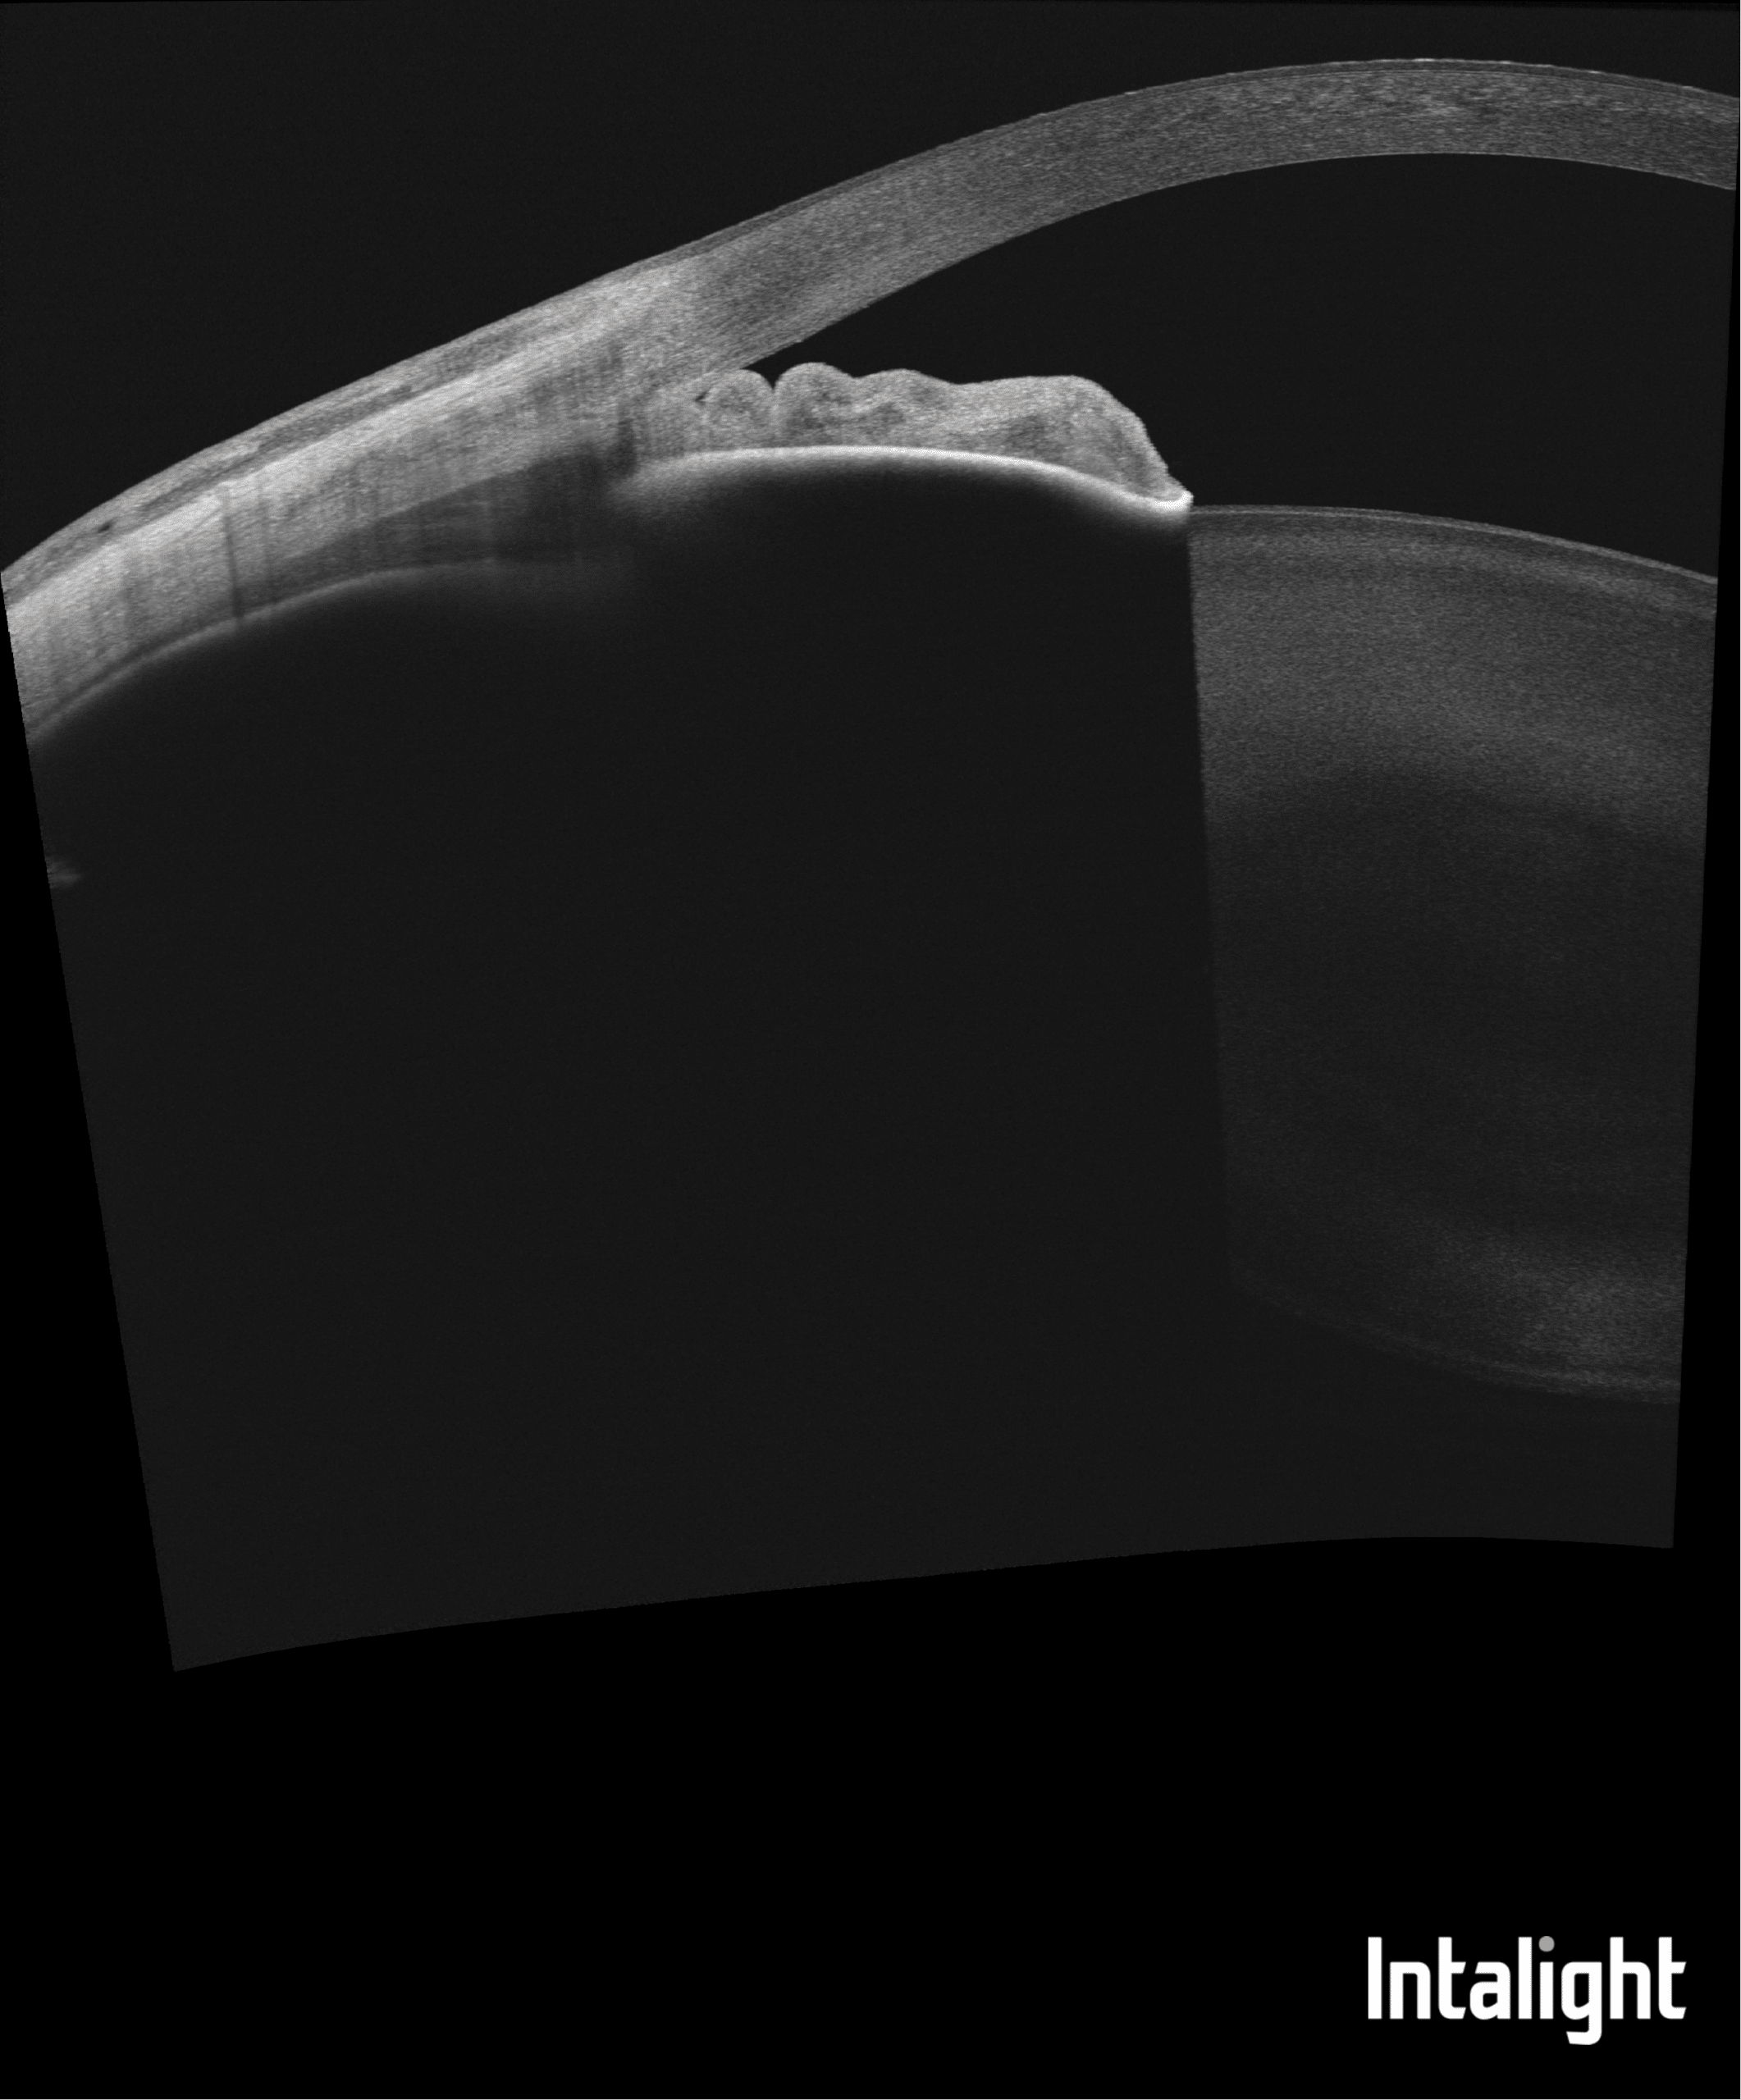

DREAM OCT : du vitré à la périphérie rétinienne

DREAM OCT : analyse grande profondeur du segment antérieur